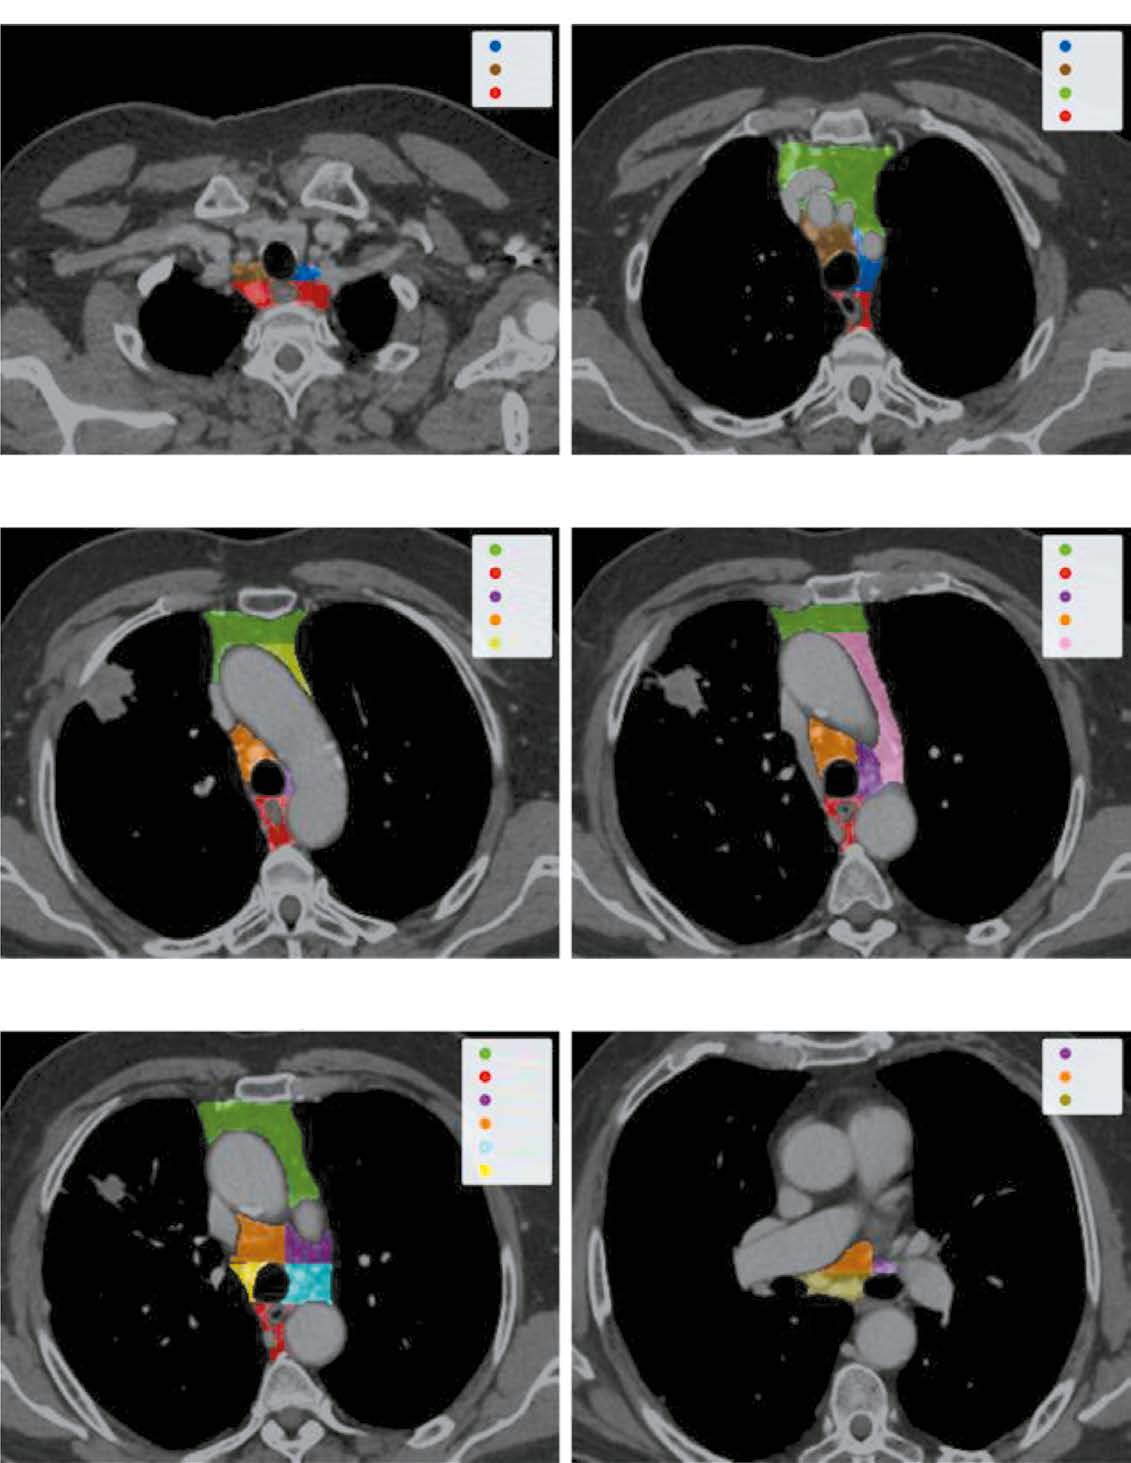

Материалы и методы. Выполнение сегментации групп лимфатических узлов в соответствии с рекомендациями Международной ассоциации по изучению рака лёгкого, чтобы получить ограничивающий прямоугольник для области средостения с целью последующей обработки данных. Затем изображение кадрируют при использовании этого ограничивающего прямоугольника и обрабатывают с помощью второй сети для выявления всех визуализируемых лимфатических узлов и генерации масок. На заключительном этапе выделяют каждый визуализируемый лимфатический узел, применяют соответствующую маску и оценивают с использованием сети прямого распространения, чтобы определить вероятность метастатического поражения.